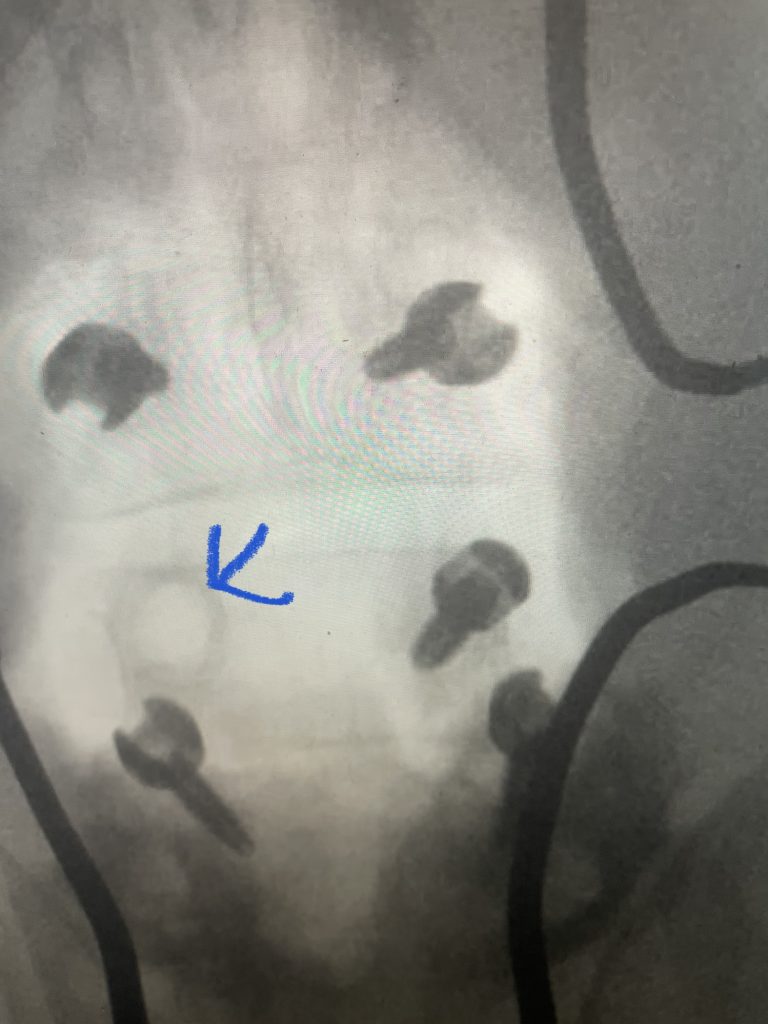

Fig 1: Upbiting curette

Revision lumbar spine surgery is amongst the most difficult of surgeries, not just in spine surgery, but of all categories of surgery. I don’t believe many spine surgeons will argue with this fact. The placement of hardware is getting slicker and easier, but there is no modern computerized technology that will improve upon the ability to separate and pick away scar tissue to establish dural planes in order to successfully decompress a patient who has redeveloped stenosis after a prior laminectomy and fusion. It does in fact take time and experience to understand what you can and can’t get away with, with regards to pressure, tension, aggressiveness of separation of planes during a dissection, and how to use the necessary tools to your advantage. A very important tool is the upbiting curette (Fig 1), which allows bone to be separated from soft material like scarred dura. This requires a very close hugging action to the undersurface of the bone of the lateral recess; if you get comfortable you can sweep an opening plane between the bone and dura since the back edge of the curette is smooth. It is important to identify opportunities of separation of planes and being patient to tend to a certain region first in order to gain the necessary plane to help you tackle another region that would have been difficult from an initial approach.